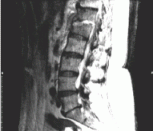

MORBIDITY AND MORTALITY

A Case of  Low Back Pain

Barry  Brenner MD, PhD, C Robinson, MD, W Duda,  MD, L Kass, MD